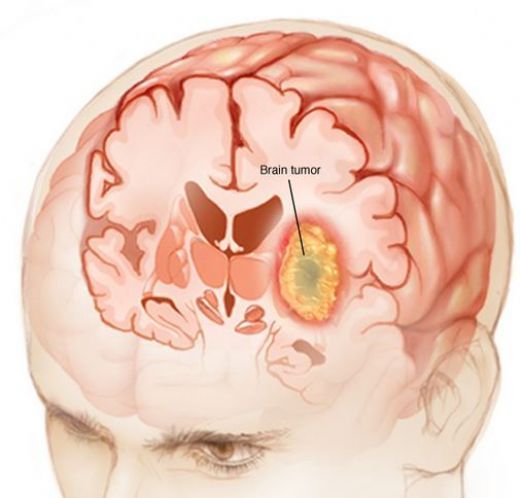

Çocuklarda beyin kanaması, çeşitli nedenlerle meydana gelebilen ciddi bir sağlık sorunudur. Bu durum, çocukların beyin dokusunun zarar görmesine ve yaşamı tehdit eden komplikasyonların ortaya çıkmasına yol açabilir. Beyin kanaması, kafatası içindeki kan damarlarının yırtılması veya sızdırması sonucu meydana gelir ve belirtileri, kanamanın türüne, yerine ve şiddetine bağlı olarak değişiklik gösterir. Beyin Kanaması Türleri Beyin kanamaları, çeşitli tiplere ayrılmaktadır. Bu türler arasında en yaygın olanları şunlardır:

Her bir kanama türü, farklı nedenlere, belirtilere ve tedavi yöntemlerine sahiptir. Belirtiler Çocuklarda beyin kanaması belirtileri, durumun ciddiyetine göre değişiklik gösterebilir. Aşağıdaki belirti ve semptomlar, beyin kanaması yaşayan bir çocukta gözlemlenebilir: